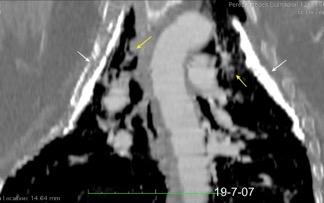

Tb con paquipleuritis calcificada, Hidroneumotórax. Cavidad apical conectada a pleura. Atelectasia redonda

Paquipleuritis calcificada bilateral. En en lado derecho toracoplastia extensa con muñón residual pulmonar con bronquiectasias.